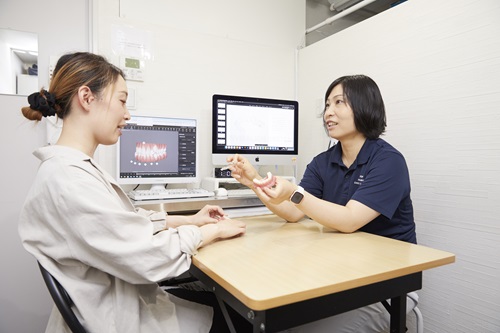

治療計画(クリンチェック)説明で行うこと

治療計画(クリンチェック)説明当日の内容をご説明します。

治療概要説明

精密検査の資料をもとに作成した『クリンチェック』で、歯の動きなどをモニターで説明いたします。

必要に応じて抜歯と非抜歯、親知らずを抜く場合と抜かない場合など、あらゆる可能性を考慮した複数のパターンをご提案することで、治療上無理がなく、より患者さまのご要望に合った治療を目指します。

治療の際に注意すべきことや、患者さまのご要望などの反映について説明いたします。

当院が目指すのは、患者さま1人ひとりに合った矯正歯科治療です。

そのために常に患者さまと1to1で向き合い、可能な限り最短期間でご要望に応えるためのプランを増やすように努めています。